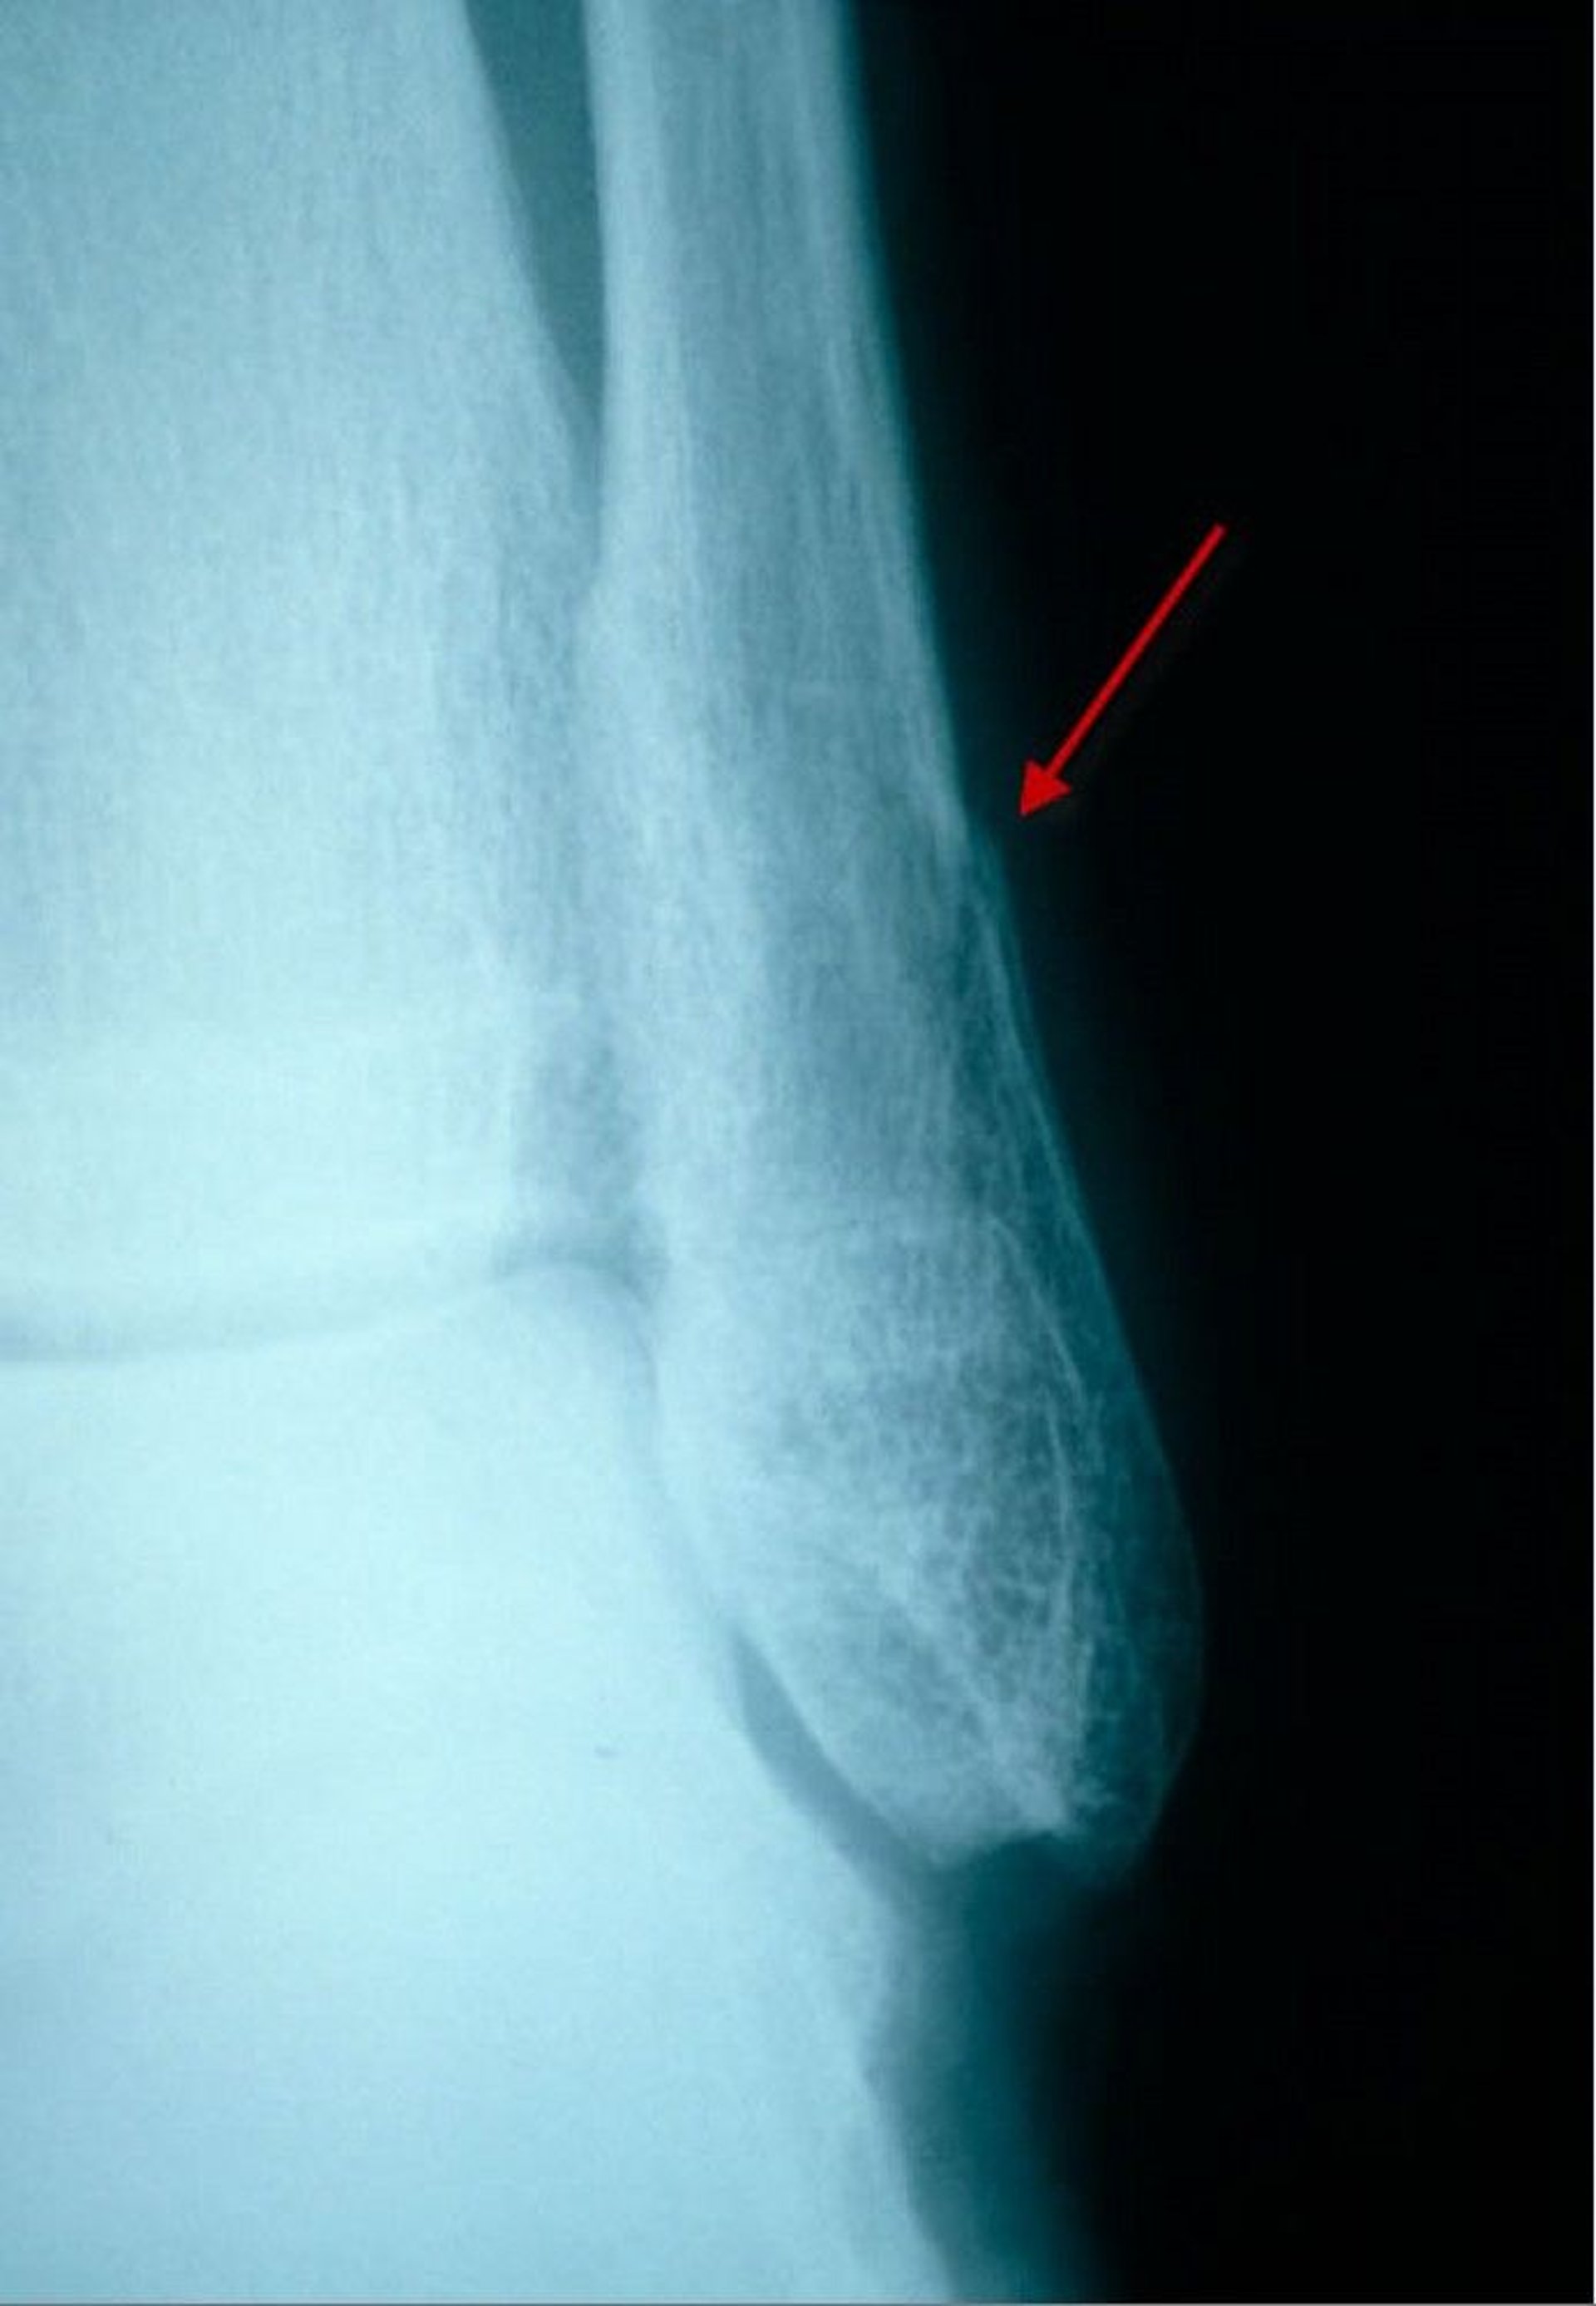

Subtle Distal Fibular Fracture (Lateral View)

In this lateral view, a fracture of the distal fibula is visible as a small lucency and discontinuity (step-off) of the cortex.